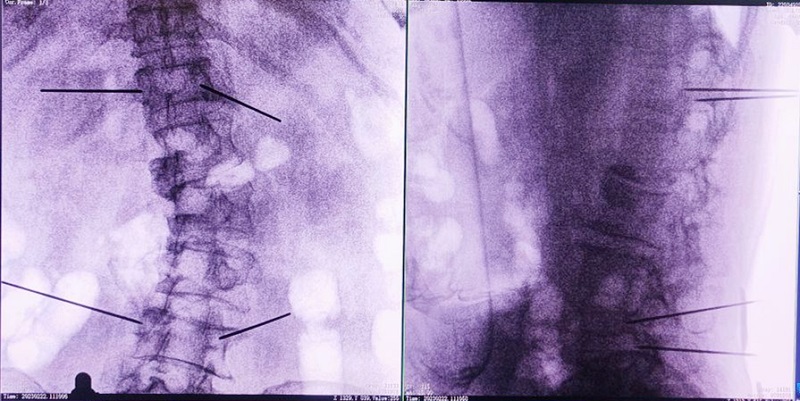

(4)所有引導(dǎo)針植入完畢后,沿引導(dǎo)針方向進(jìn)行椎弓根及椎體置管,建立通道;

(5)沿通道注入骨水泥,恢復(fù)椎體高度,并觀察其擴(kuò)散情況,達(dá)到滿意效果后,停止注入骨水泥。